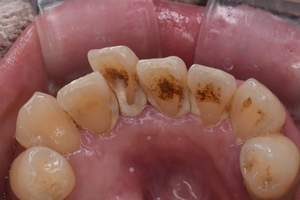

PMTC

治療前

治療後

| 年齢 | 50歳・男性 |

| 主訴 | 着色をとりたい |

| 治療内容 | PMTC |

| 治療期間 | 30分 |

| 費用 | PMTC 5,500円(自費診療) |

| リスク・副作用 | ・生活習慣(喫煙・コーヒーなど)により再度着色することがあります ・PMTCは歯を白くするものではなく着色・バイオフィルムの除去を目的としています ・保険適用外の施術です |